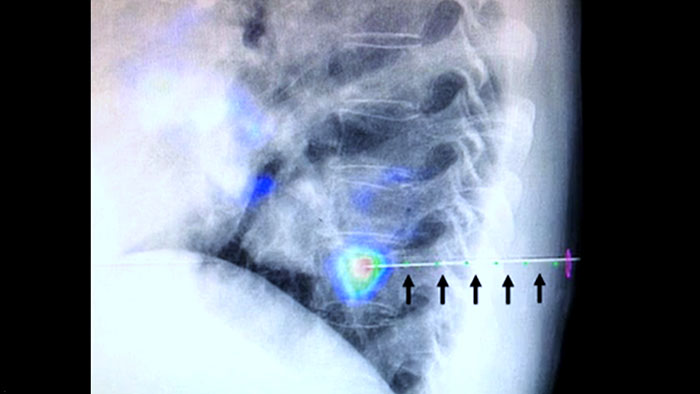

Dual View permite la superposición de una imagen 3D previa al procedimiento (TC/RM/PET) sobre una CBCT Dual 3D intraprocedimiento para visualizar mejor las lesiones y acceder a información crítica para la planificación de la trayectoria de la aguja.

XperGuide proporciona una guía de imagen en vivo de alta precisión de cada aguja a una posición determinada mediante la superposición de trayectorias preplanificadas con imágenes fluoroscópicas.3